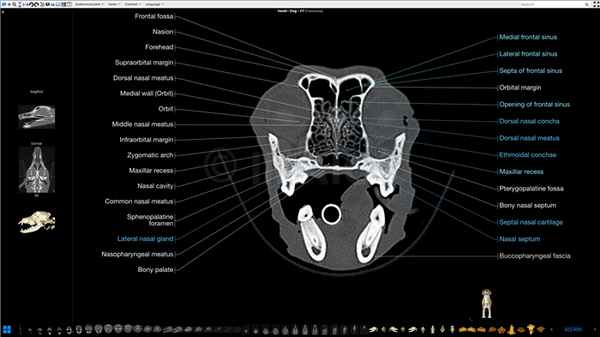

Анатомия головы и черепа собаки в КТ-срезах (кости черепа, мозг, мышцы лицевой части, гортань, глотка, синус лицевой части черепа)

В этом модуле атласа анатомии животных представлены КТ-изображения головы пятилетнего лабрадора в поперечной, сагиттальной и дорсальной (фронтальной) плоскостях, а также 3D-реконструкция костей и кожи. Исследования проводились доктором Сюзанной АЕБ Бороффка (англ. Dr. Susanne AEB Boroffka, PhD), дипломированным специалистом ECVDI (Утрехт, Нидерланды).

Анатомические структуры (740 элементов) с названиями сгруппированы в разделы:

Латинские анатомические термины соответствуют Международной ветеринарной анатомической номенклатуре Nomina Anatomica Veterinaria (пятая редакция - 2012 ICVGAN) и переведены на английский и французский языки Антуаном Мишо (фр. Dr. Antoine Micheau) − Imaios.

Латинские анатомические термины соответствуют Международной ветеринарной анатомической номенклатуре Nomina Anatomica Veterinaria (пятая редакция - 2012 ICVGAN) и переведены на английский и французский языки Антуаном Мишо − Imaios.